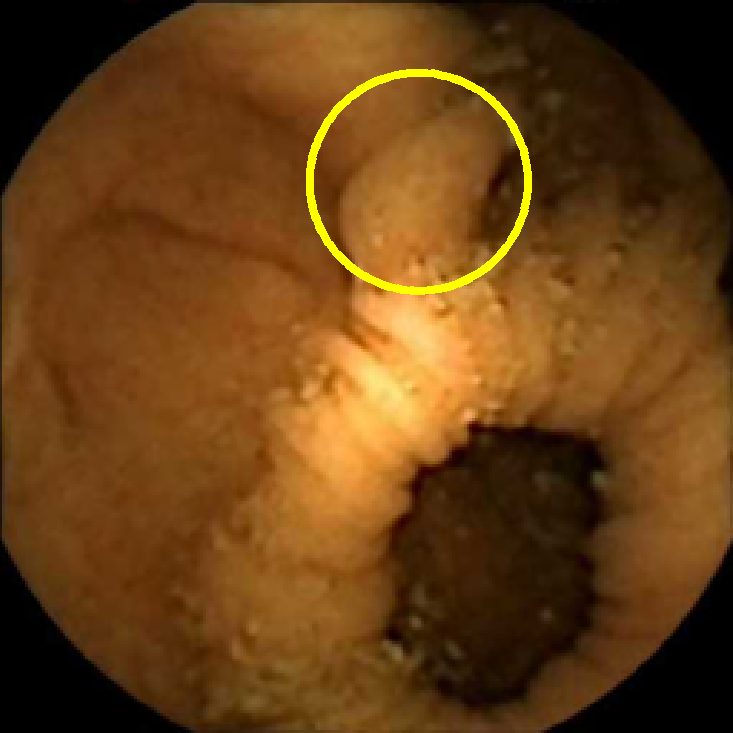

In Figure 5 we show the circles of radius corresponding to the features that were correctly classified as polyps by (29). We observe that the classifier was able to identify the polyps of a variety of shapes even in the presence of small amounts of trash liquid (first row) or when the polyps are located next to mucosal folds (rows two to four in column (c)).

The examples of incorrect classification of frames are presented in Figure 6. The first two examples show false negatives, each highlighting a possible source of classification error. The example in column (a) shows the case where the feature corresponding to the polyp was too stretched out and thus was rejected by the eccentricity criterion (21). In contrast, the feature corresponding to the polyp in column (b) has passed the combined geometric criterion (22), but the radius was below the threshold of the binary classifier. Examples in columns (c) and (d) show the two sources of possible false positives. The false positive detection in column (c) is due to insufficient illumination correction. The bright spot is not fully corrected at the pre-processing stage and subsequently generates a polyp-like feature in the mid-pass filtered frame that happens to pass through all the criteria. Finally, in column (d) a mucosal fold is classified as polyp. Note that such cases are the most difficult to deal with, as the mucosal folds can often be hard to distinguish from polyps even for a human operator.